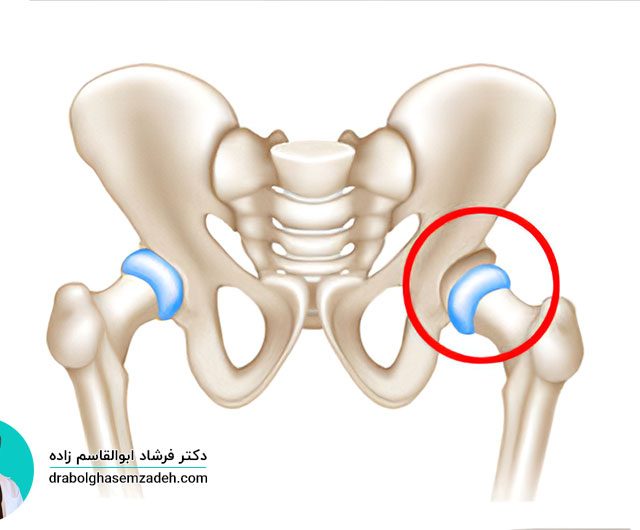

روماتیسم مفصلی نوعی بیماری است که موجب درد، التهاب و تورم مفصل های بدن می شود و مفصل لگن نیز از این قاعده مستثنی نیست. درمان روماتیسم لگن می تواند از مشکلات بسیاری از جمله تخریب مفصل لگن پیشگیری کند. این بیماری در زنان شایع تر از مردان است و علائم بیشتری از خود نشان […]...